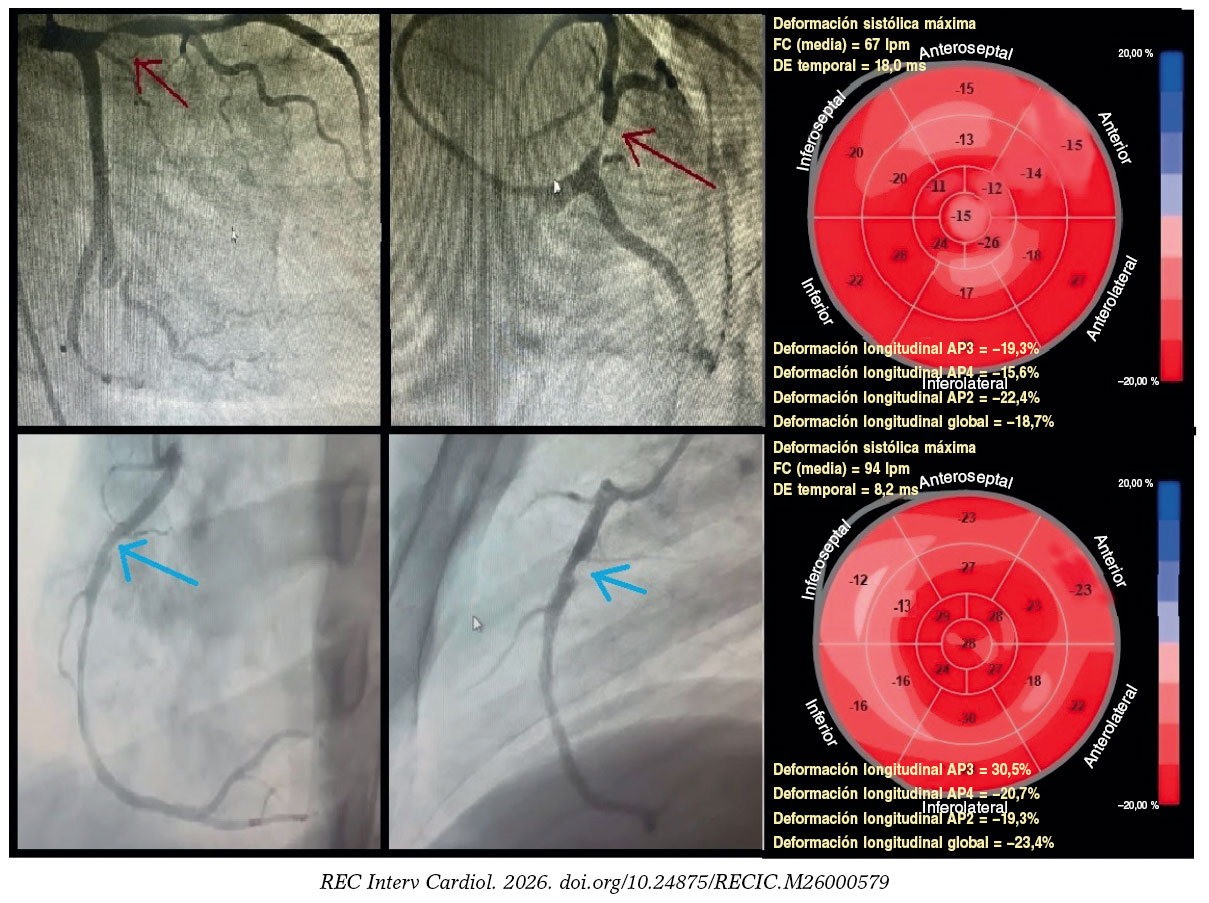

Figura 4. Deformación longitudinal territorial en participantes con cardiopatía isquémica estable. Fila superior: participante representativo del estudio con lesión proximal significativa en la descendente anterior (porcentaje de estenosis por diámetro ≥ 70%; flecha roja). La deformación longitudinal global fue del −18,7%. Siete segmentos dentro del territorio de la descendente anterior (segmentos anteroseptales, anteriores y ápex) mostraron deformación alterada (≥ −16%), lo cual corresponde a verdaderos positivos, mientras que los territorios de la circunfleja izquierda y la coronaria derecha presentaron deformación conservada (< −16%), lo cual corresponde a verdaderos negativos. Fila inferior: participante representativo del estudio con una lesión proximal significativa en la coronaria derecha (porcentaje de estenosis por diámetro ≥ 70%; flecha azul). La deformación longitudinal global fue del −23,3%. Cuatro segmentos dentro del territorio de la coronaria derecha (segmentos medio, basal inferior e inferoseptal) mostraron deformación alterada (≥ −16%), lo cual corresponde a verdaderos positivos, mientras que los territorios de la descendente anterior y la circunfleja izquierda presentaron deformación conservada (< −16%), lo cual corresponde a verdaderos negativos.